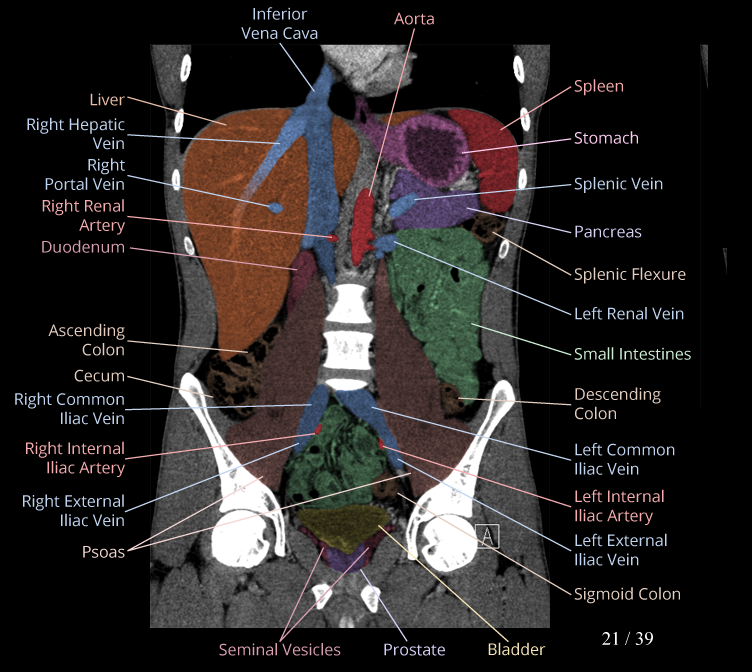

Body

Covers abdominal CT anatomy.